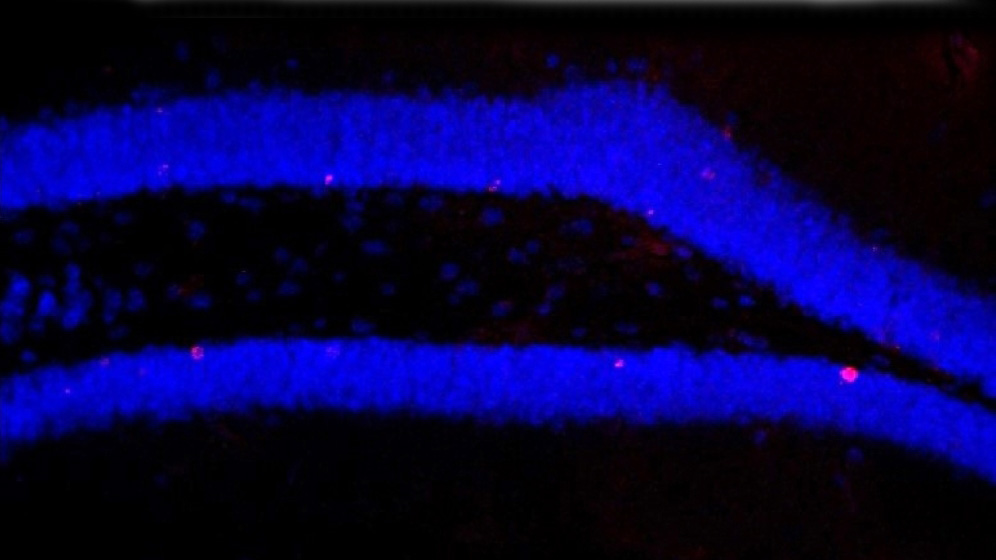

In Mäusen schalteten die Forschenden das Mikrobiom, also die Bakterien der Darmflora, mit einem Antibiotika-Cocktail aus. Verglichen mit unbehandelten Tieren beobachteten sie daraufhin deutlich weniger neu gebildete Nervenzellen in der Hippocampus-Region des Gehirns. Auch das Gedächtnis der Mäuse verschlechterte sich, denn diese Bildung neuer Hirnzellen – „Neurogenese“ genannt – ist wichtig für bestimmte Gedächtnisleistungen.

Bei ausgeschaltetem Mikrobiom ging zusammen mit der Neurogenese auch die Zahl einer bestimmten Immunzellen-Population im Gehirn deutlich zurück, die der Ly6C(hi)-Monozyten. Könnten diese Immunzellen ein bislang unbekannter Vermittler zwischen den Organsystemen sein? Wolf und ihr Team testeten und bestätigten diese Hypothese: Entfernten sie nur diese Zellen aus den Mäusen, verringerte sich die Neurogenese ebenfalls. Verabreichte sie den mit Antibiotika behandelten Tieren Ly6C(hi)-Monozyten, nahm die Neurogenese wieder zu.